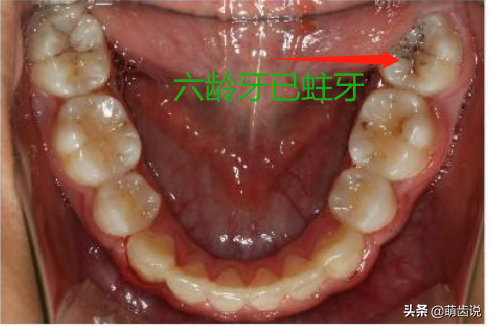

【情景三】恒牙(六龄牙)龋坏

家长:“医生,我们孩子最里面的大牙蛀了,你看看还要多久换牙?”

医生:“这是恒牙!再也不换了,现在已经蛀了,要赶紧治疗了……”

话没说完,家长就激动了:“怎么可能!这颗牙都没换过,怎么会是恒牙?医生,你能分辨乳牙和恒牙吗?”

乳恒牙交替时期,极其容易被忽视的六龄牙!